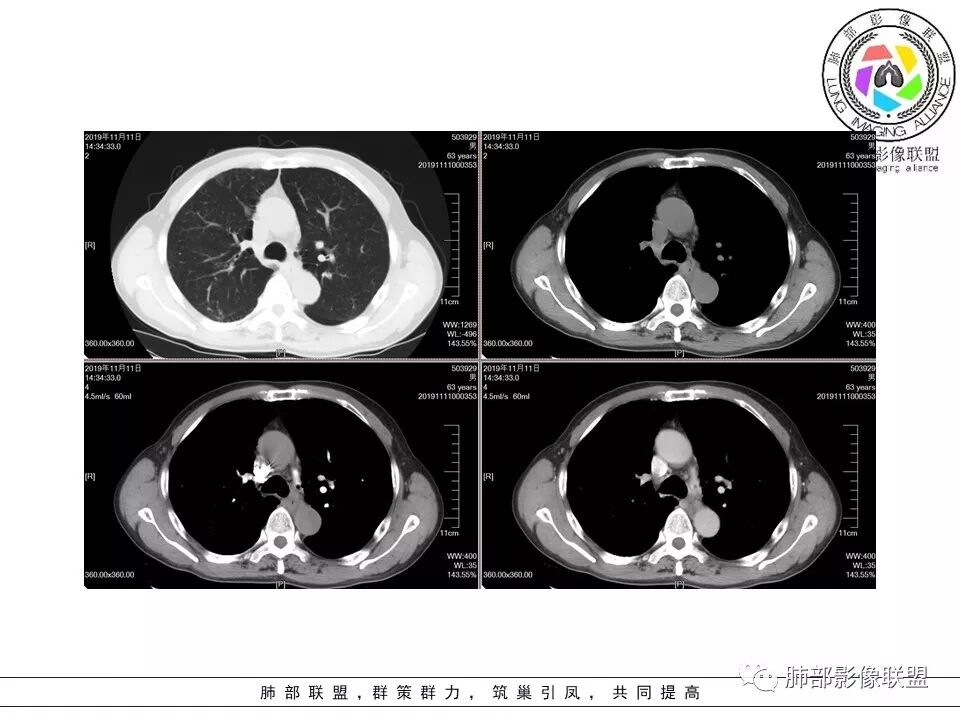

大雄:老年男性,有类风湿病史,长期服用激素,无阳性主诉CT示右肺上叶后段及左肺下叶基底段胸膜下多结节影,境界清晰,边缘毛糙,整体收缩,长轴与胸膜平行,增强扫描轻中度均匀强化。考虑炎性病变,建议查隐球荚膜多糖滴度试验

晕晕菜:患者中老年男性,体检发现肺部占位。既往既往有类风湿关节炎,长期口服激素胸CT:间隔旁肺气肿,右肺上叶后段胸膜下病变,与胸膜宽基底相连,局部胸膜明显增厚,病灶内可见空洞,病灶周围有散在卫星灶。左肺下叶背段胸膜下实变,病灶边界清楚,与长轴与胸膜平行,病灶周围可见软毛刺,纵隔窗可见病灶与胸膜呈糊墙征。 总体考虑良性病变。右上:结核?左下:隐球菌?

没意见:老年男性,明确有风免疾病背景,长期激素治疗,CT:双肺下叶外周多发结节,大部分宽基底胸膜相连,长轴垂直支气管,刀切平直,密度较为均匀,近心端空洞,强化程度目测略低,下肺背侧网格、磨玻璃、小蜂窝,考虑炎性结节,至于是感染还是风湿结节难度较大,需要结合临床来进一步确认

小赵:老年男性,类风湿及长期服药史。胸部CT所见右肺上叶及左肺下叶胸膜下多发病灶,右肺上叶病灶内见空洞及液平面,内壁光滑,周围散在条索及小结节样卫星灶,邻近胸膜增厚,增强扫描病灶轻度强化。左肺下叶病灶长轴平行于胸膜,周围见边界不清磨玻璃密度影,与邻近胸膜成糊墙改变。增强扫描病变成不均匀明显强化,内见强化血管影。诊断一元考虑双肺炎性病变,隐球菌可能。二元考虑右肺上叶结核,左肺下叶隐球菌感染,粘液腺癌待排。

菲菲菲:男,63,体检发现肺占位,既往类风湿性关节炎13年,双肺胸膜下多发斑片及结节影,右肺下叶病灶内见偏心性小空洞形成,周围有卫星灶,胸膜增厚,左肺下叶病灶轻度强化,纵隔内无肿大淋巴结,考虑炎性病变。隐球菌鉴别结核

一米阳光:双肺胸膜下多发结节病影,小结节融合,病灶与胸膜面平行,垂直支气管,边缘模糊,晕征,支气管进入堵塞,内见小空洞,增强均匀强化。结合病史,有类风湿病史,考虑炎性肉芽肿,隐球菌感染。鉴别,结核建议,穿刺,隐球荚膜抗原检查

破风5:胸部CT:右上叶胸膜下病变,与胸膜宽基底相连,累及胸膜,病灶内可见空洞,洞壁光滑,病灶周围有散在卫星灶。有类风湿激素口服历史,结核首先考虑。左肺下叶背段胸膜下实变,病灶边界清楚,与长轴与胸膜平行,血管伸入,纵隔窗可见糊墙征。考虑良性病变,隐球?总体,右上肺结核,左下肺隐球,CTD-ILD

流心明智:患者,老年男性,既往有类风湿关节炎,长期口服激素史。胸CT:间隔旁肺气肿,右肺上叶后段胸膜下病变,与胸膜宽基底相连,局部胸膜增厚,病灶内向肺门侧空洞,病灶周围卫星灶。考虑炎性病灶。左肺下叶胸膜下气肿背景边缘实变、边界清楚、有膨隆、滋养血管征,软毛刺、多结节融合、糊墙征。 总体考虑:良性病变,右上:结核?左下:隐球菌?左下鉴别Ca。

南边:病灶很多,一元?2元?3元?

南边:

南边:类风湿性肺纤维化——NSIP

右上叶边缘收缩,宽基底与胸膜相连,胸膜增厚,附近索条,支持炎性

南边:糊墙,长轴与胸膜平行;边缘收缩+膨隆;脐凹征

常规:隐球菌与癌鉴别

脐凹征,高度提示恶性

因为其与胸膜的关系与右上叶的不一致,所以不能一元论

而且周围的表现不一致

还有就是间质性病变基础上,恶性变的几率很高

病理结果:巨细胞癌。